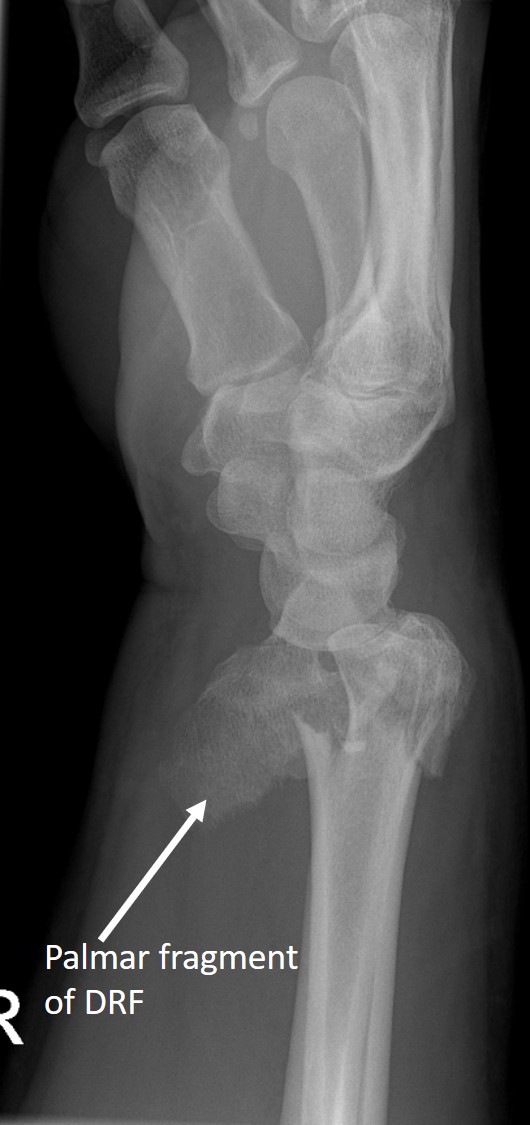

High-energy distal radius fractures are characterized by significant displacement of bone fragments, articular surface damage, and ligamentous injury. Tendon interposition between bone fragments occurs very rarely. In this report, we present a case of a complex distal radius fracture in which intraoperative findings revealed interposition of the flexor digitorum superficialis tendon of the index finger beneath one of the fracture fragments. The exceptional rarity of this situation prompted the authors to report this case.